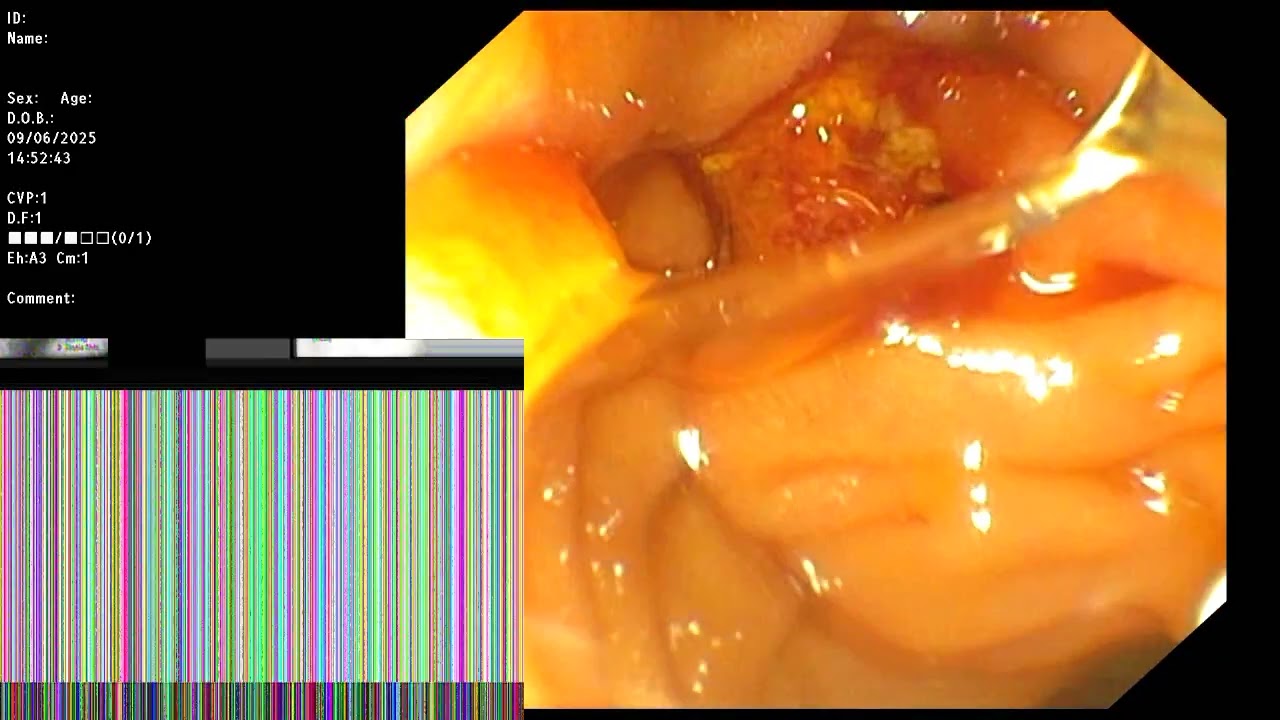

ERCP ; CBD stone obstruction with suppurative cholangitis.